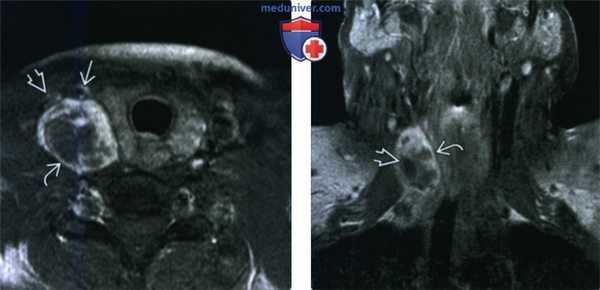

(Слева) КТ с КУ, аксиальная проекция. Образование овальной формы в заднемедиальном отделе сонного пространства. Обратите внимание, что сонная артерия находится на передней поверхности опухоли, а внутренняя яремная вена - на латеральной. Незначительное накопление контраста не очень характерно для шванном, в данном случае вид опухоли напоминает нейрофиброму.

(Справа) MPT Т2ВИ, аксиальная проекция. Округлое образование с неоднородным сигналом, которое смещает общую сонную артерию кпереди. Внутренняя яремная вена смещена вместе с артерией. При сдавливании яремной вены ее идентификация может быть затруднена.

(Слева) МРТ Т1ВИ FS с КУ, аксиальная проекция. В задних отделах подподъязычного сонного пространства расположено образование округлой формы. Шваннома симпатического ствола смещает и сонную артерию, и внутреннюю яремную вену кпереди. Одновременное смещение обоих сосудов сонного пространства весьма характерно для шванномы симпатического ствола.

(Справа) МРТ Т1ВИ FS c КУ, коронарная проекция. Шваннома симпатического ствола, расположенная в сонном пространстве. Опухоль неравномерно накапливает контрастное вещество. Участки кистозного перерождения в крупных шванномах встречаются достаточно часто.